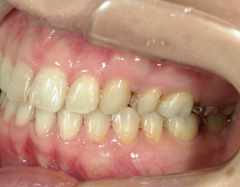

矯正歯科 治療前

36歳女性 磐田市

在住

治療期間2年6

ヶ月